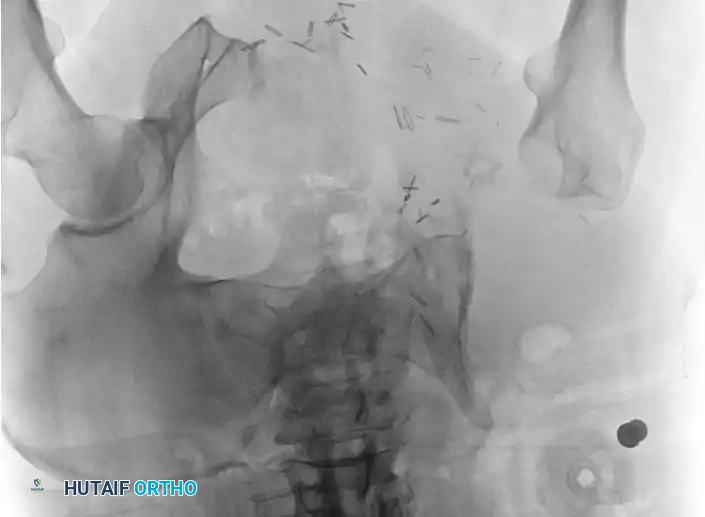

Intraoperative Imaging and Margin Assessment

Continuous intraoperative assessment using fluoroscopy and frozen section pathology is mandatory. The following images demonstrate various stages of complex upper extremity resections, allograft preparations, and prosthetic implantations across the humerus and elbow joint.